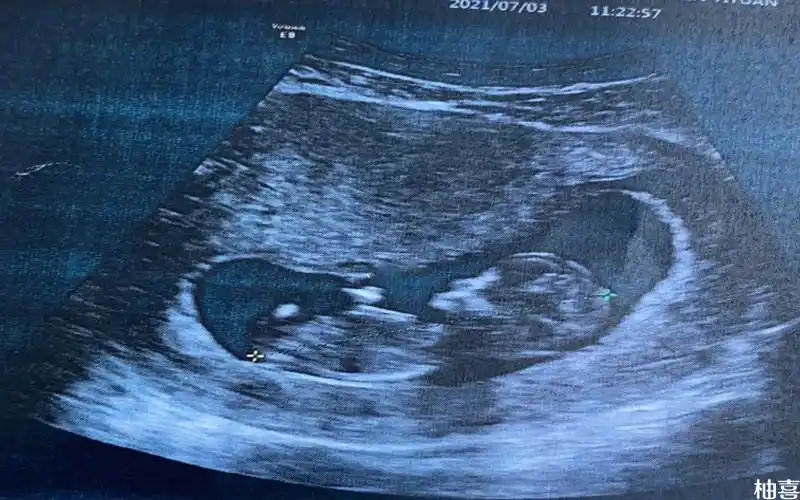

nt图像上有三个点是怀女孩的概率更高吗?